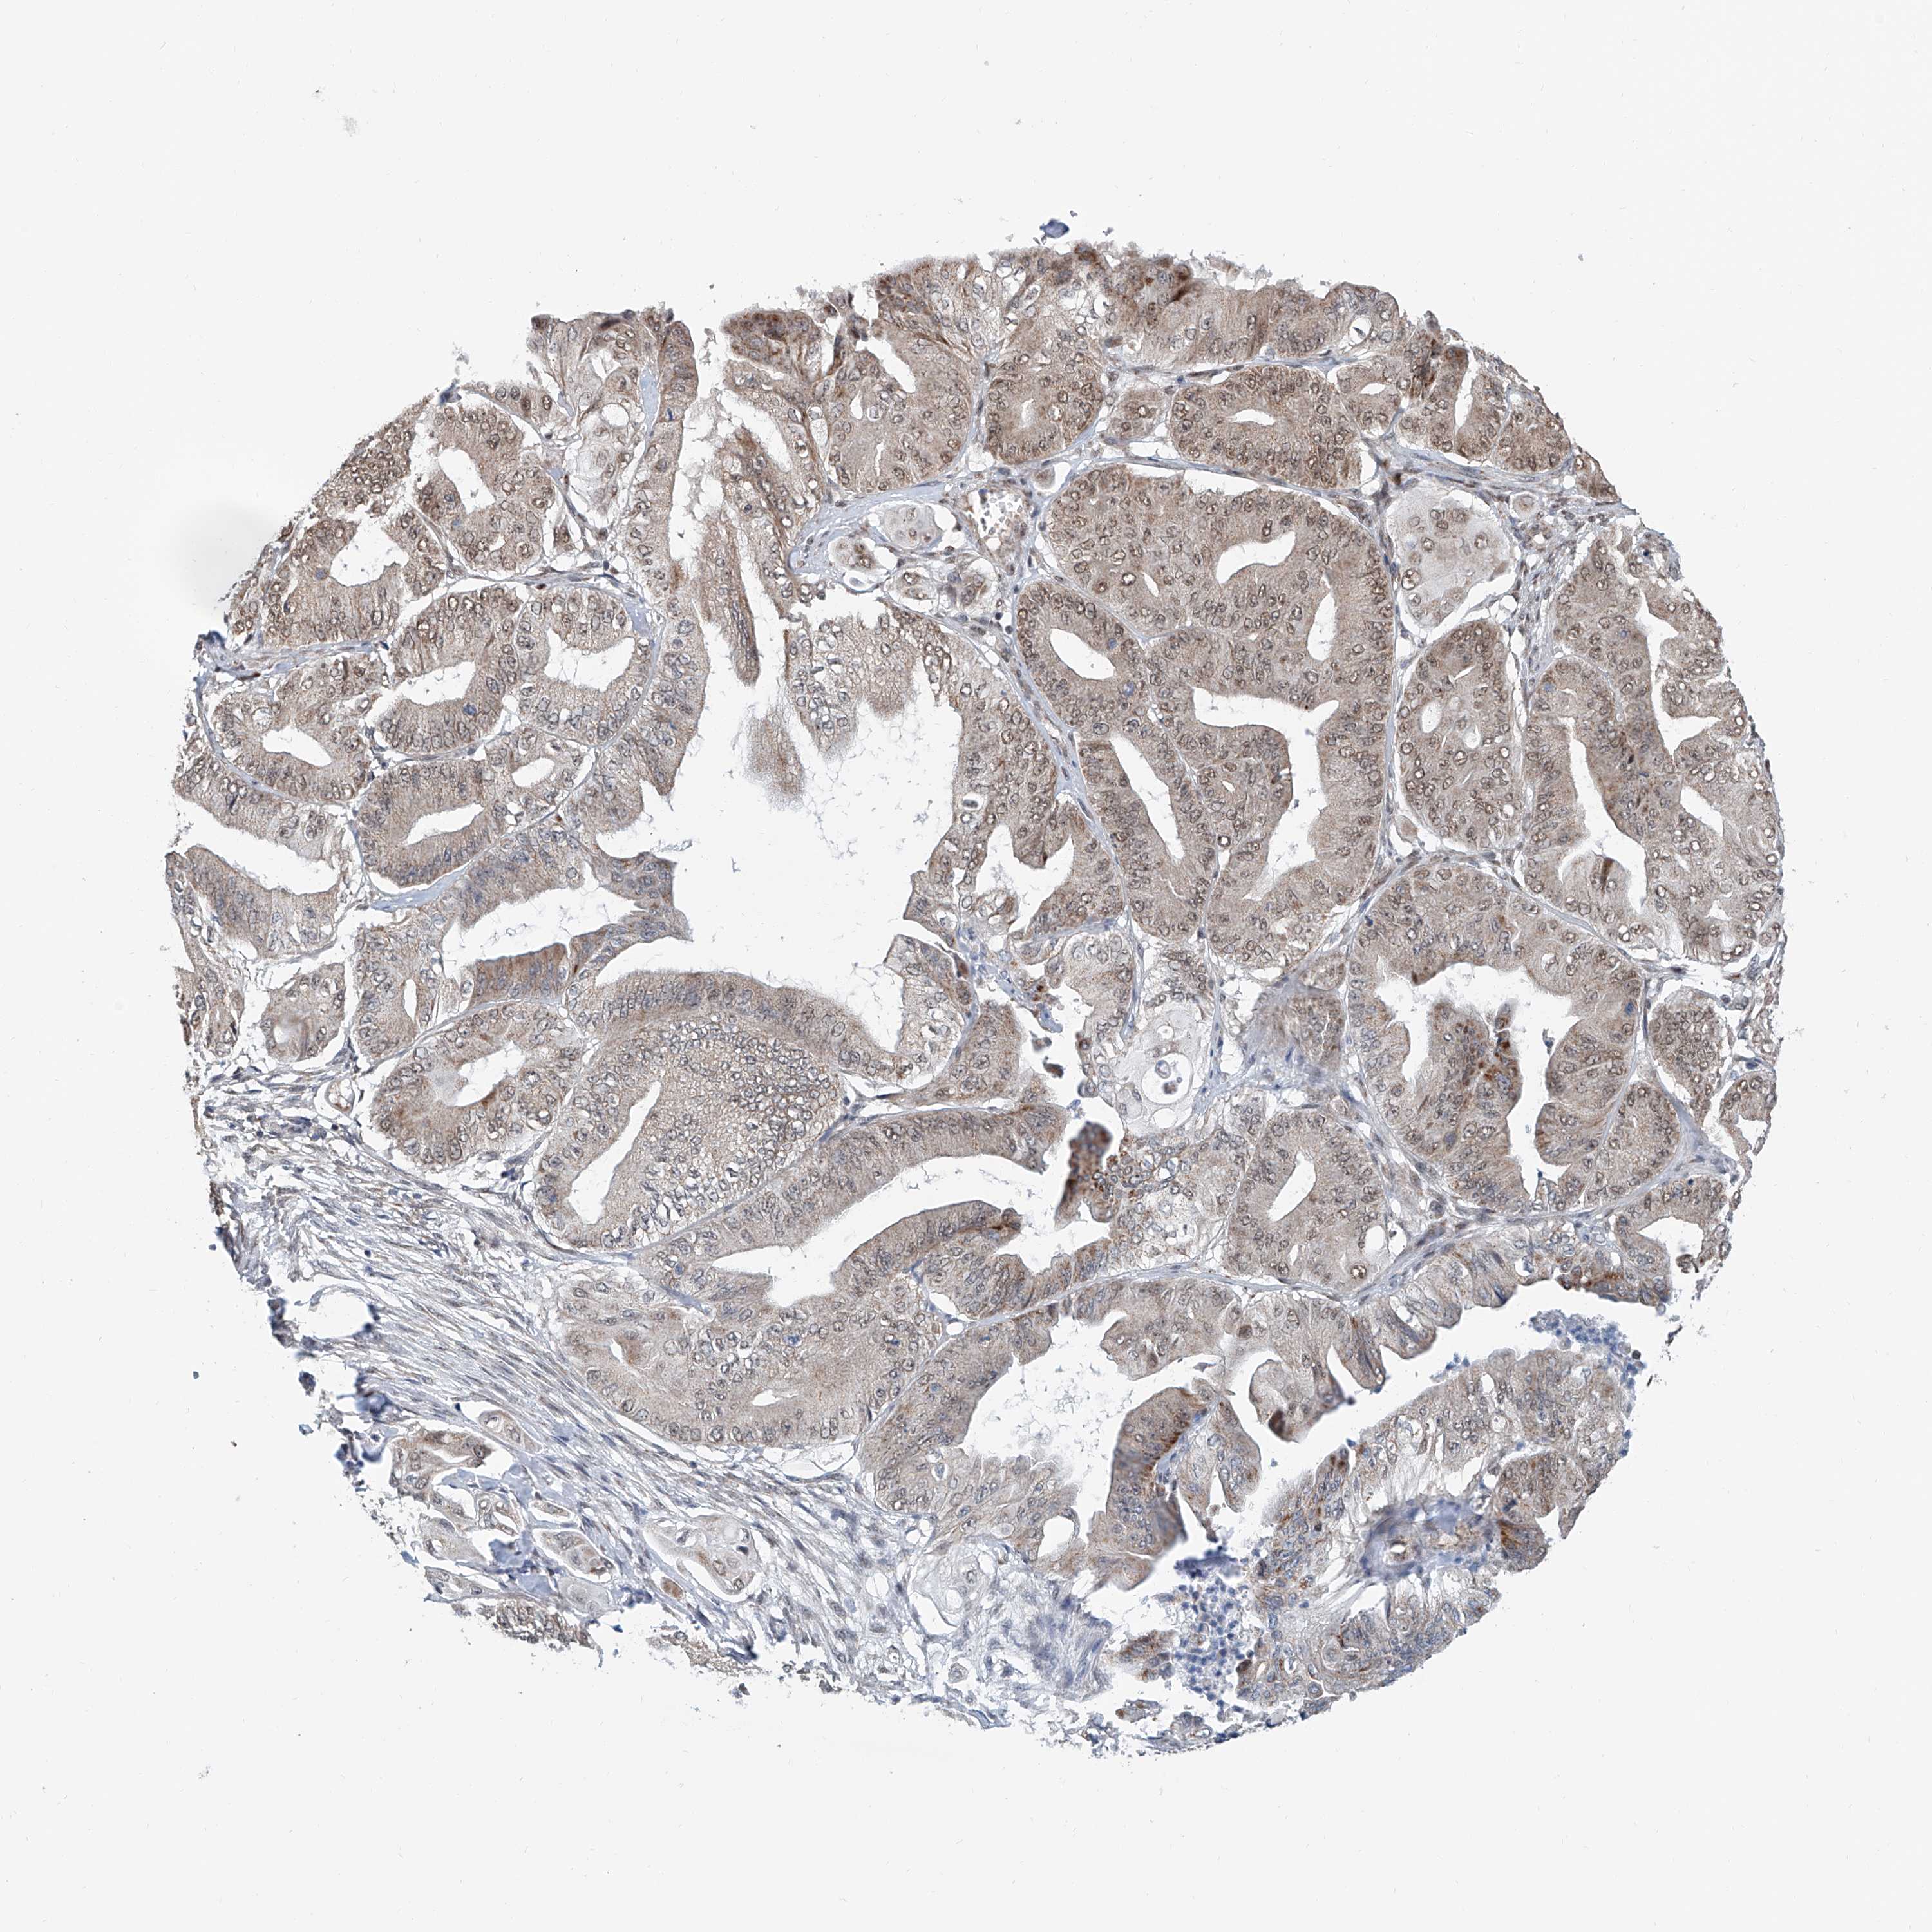

PANCREATIC CANCER - Protein expressioni

A mouse-over function shows sample information and annotation data. Click on an image to view it in a full screen mode. Samples can be filtered based on level of antibody staining by selecting one or several of the following categories: high, medium, low and not detected. The assay and annotation is described here.

Note that samples used for immunohistochemistry by the Human Protein Atlas do not correspond to samples in the TCGA dataset.

Antibody stainingi

Antibody staining in the annotated cell types in the current human tissue is reported as not detected, low, medium, or high, based on conventional immunohistochemistry profiling in selected tissues. This score is based on the combination of the staining intensity and fraction of stained cells.

Each image is clickable and will lead to virtual microscopy that enables deeper exploration of all samples and also displays staining intensity scores, fraction scores and subcellular localization as well as patient and tissue information for each sample.

Antibody HPA028467

Antibody HPA031255

Antibody HPA031256

Staining

High

Medium

Low

Not detected

Intensity

Strong

Moderate

Weak

Negative

Quantity

>75%

75%-25%

<25%

None

Location

Nuclear

Cytoplasmic/membranous

Cytoplasmic/membranous,nuclear

Adenocarcinoma, NOS